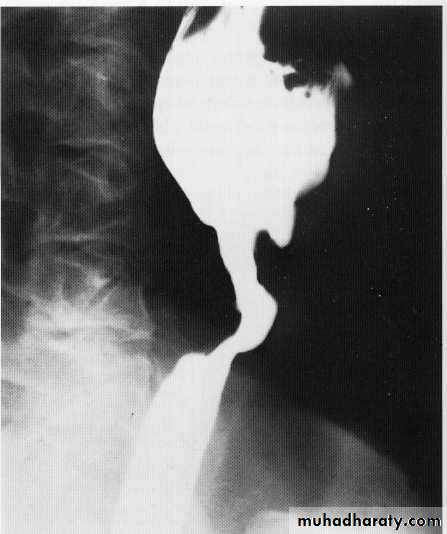

sliding HH

Para esoph. HHNormal extrinsic compression